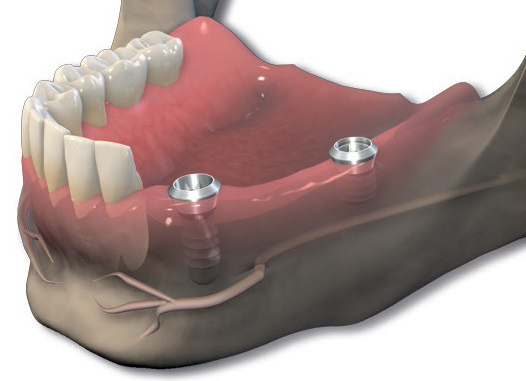

EDENTULISMO TOTAL

-

Sobredentadura. Es importante destacar que esta modalidad de tratamiento se perfila como una opción REMOVIBLE, es decir, una vez colocados los implantes (su número varía desde un mínimo de 2 a un máximo de 4 en la mandíbula y un mínimo de 4 en el maxilar) la prótesis se asentará y ajustará sobre ellos de una manera firme y estable, pero el paciente podrá retirarla siempre que lo desee. Relativamente voluminosa, la prótesis repone la totalidad de los dientes ausentes así como los tejidos perdidos como consecuencia del proceso de reabsorción ósea que se desencadena tras la pérdida dentaria.

Este tipo de tratamiento se recomienda, siempre que la disponibilidad ósea lo permita, a aquellos pacientes con un marcado grado de reabsorción ósea; la aleta vestibular de la prótesis les devolverá el soporte labial perdido.